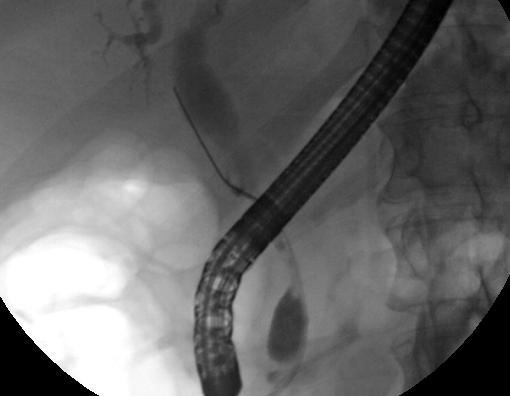

복부 영상은 담관암 진단에 유용하지만, 담관을 직접 촬영하는 것이 필요한 경우가 많다. 내시경 역행성 담췌관 조영술(ERCP)은 소화기내과 전문의 또는 특수 훈련을 받은 외과의가 시행하는 내시경 시술로, 이러한 목적으로 널리 사용된다. ERCP는 침습적인 시술로 위험성이 수반되지만, 생검을 하고 스텐트를 삽입하거나 담도 폐쇄를 완화하기 위한 기타 중재를 수행할 수 있다는 장점이 있다.[163] 내시경 초음파는 ERCP 시에도 시행할 수 있으며 생검의 정확성을 높이고 림프절 침범 및 수술 가능성에 대한 정보를 얻을 수 있다.[164] ERCP의 대안으로 경피 경간 담관 조영술(PTC)을 사용할 수 있다. 자기공명 담췌관 조영술(MRCP)은 ERCP의 비침습적 대안이다.[165][166][167] 일부 저자는 MRCP가 종양을 더 정확하게 정의할 수 있고 ERCP의 위험을 피할 수 있으므로 담도암 진단에서 ERCP를 대체해야 한다고 제안했다.[168][169][170]